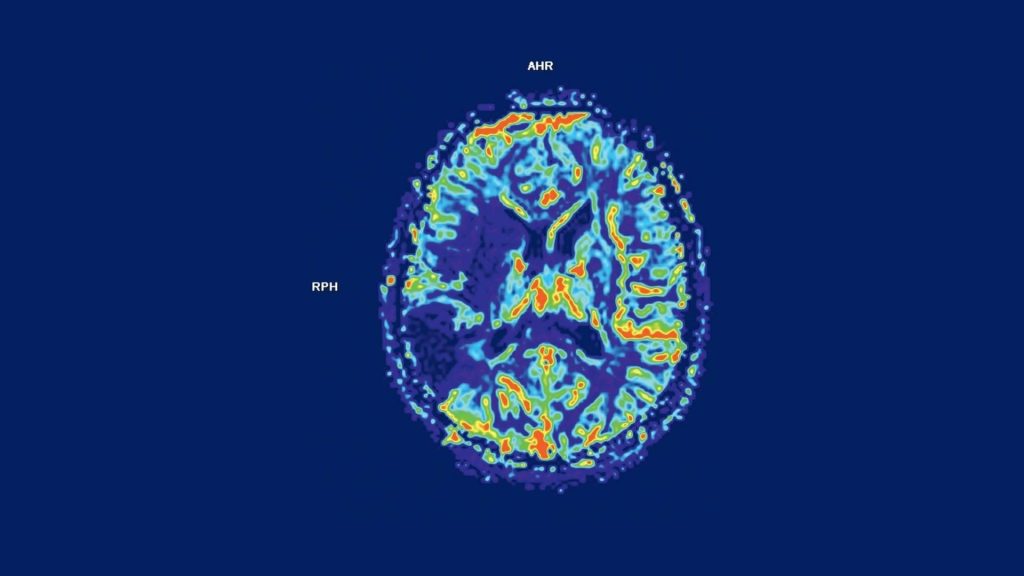

Investigaţii neuroimagistice speciale. Aplicații în patologia neurologică

Autor: Dr. Mircea Medrea Investigaţii neuroimagistice speciale. Aplicații în patologia neurologică I. PWI (PERFUSION WEIGHTED…